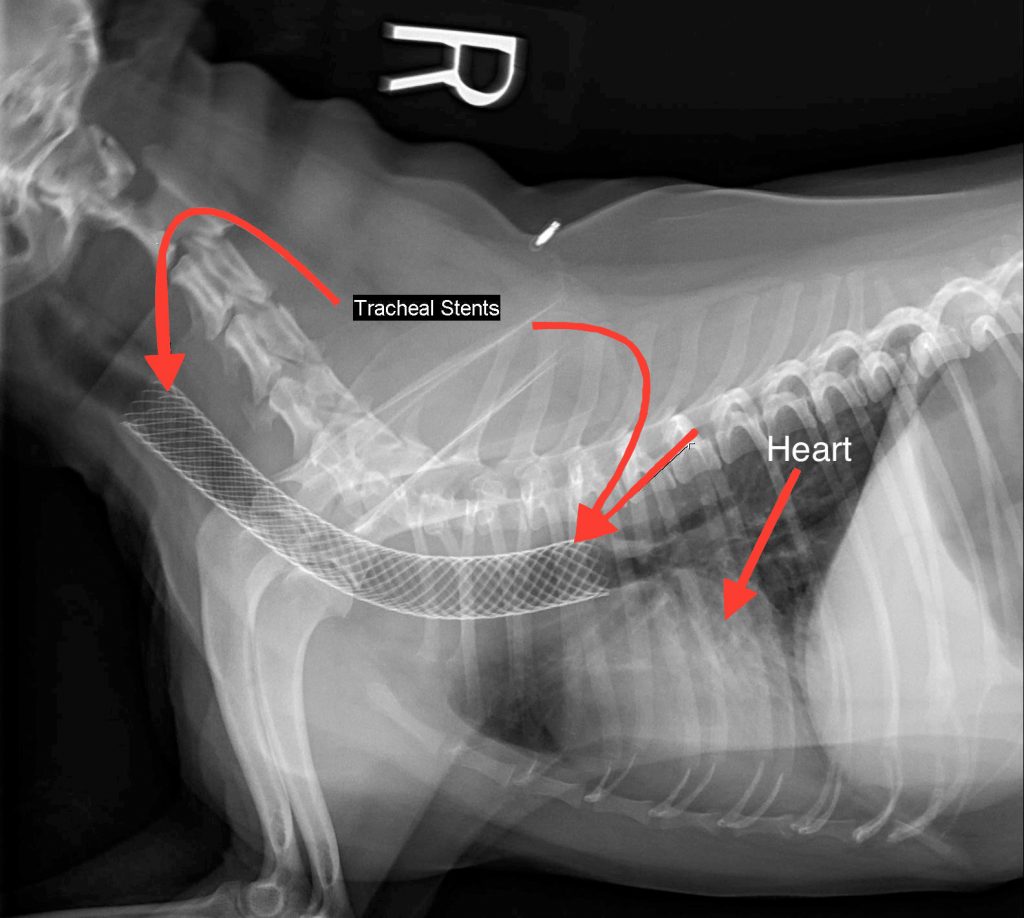

1. Tracheal Stent Placement

This is one of the most common surgical interventions for collapsed trachea. The procedure involves:

- Inserting a mesh-like sleeve (stent) into the trachea

- The stent expands to reinforce the trachea and keep it open

- It’s generally less invasive than other surgical options

- Can be performed through the mouth without external incisions

This procedure has shown good success rates, with one study showing stainless steel, self-expanding rings having a 96% success rate.